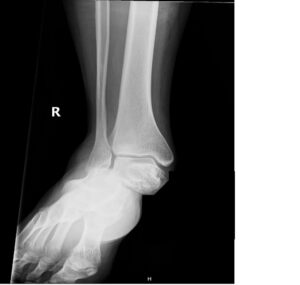

Subtalar Dislocation. Subtalar dislocation, AP unannotated. JETem 2024

Subtalar Dislocation. Subtalar dislocation AP unannotated. JETem 2024